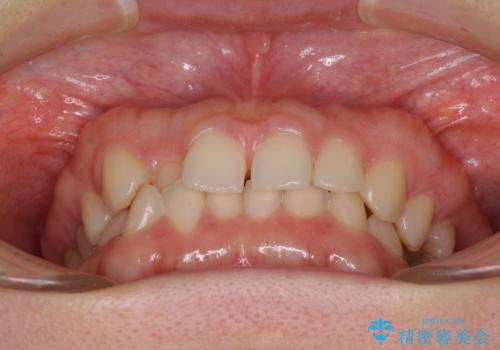

- 前歯の隙間やクロスバイトを気にして来院された患者様です。

結婚式の予定があり、可能であれば結婚式までに治療を終えたいとのことで、短期間で治療をおける可能性の高いワイヤー装置にて矯正治療を行うこととしました。